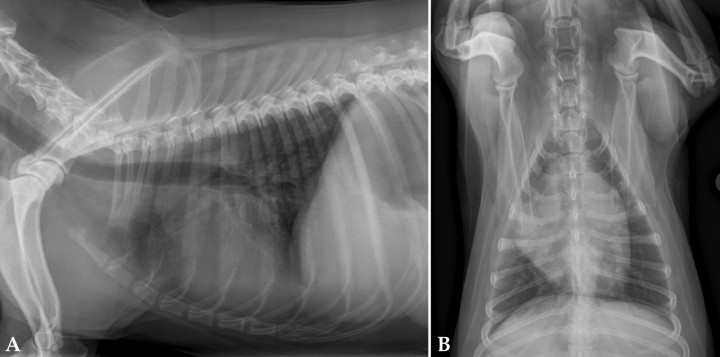

- Derrame pericárdico (Fig. 4): produce una imagen globosa del corazón con desplazamiento dorsal de la tráquea e hipoperfusión pulmonar.

<p>Radiografías de la cavidad torácica de un paciente con derrame pericárdico. (<strong>A</strong>) Lateral. (<strong>B</strong>) Ventrodorsal.</p>

Radiografías de la cavidad torácica de un paciente con derrame pericárdico. (A) Lateral. (B) Ventrodorsal.

- Aumento de tamaño de base cardiaca (Fig. 5): se observa un desplazamiento dorsal de tráquea y aumento de tamaño en la proyección dorsoventral.

<p>Radiografías de la cavidad torácica de un paciente con tumor de base cardiaca. (<strong>A</strong>) Lateral. (<strong>B</strong>) Ventrodorsal.</p>

Radiografías de la cavidad torácica de un paciente con tumor de base cardiaca. (A) Lateral. (B) Ventrodorsal.